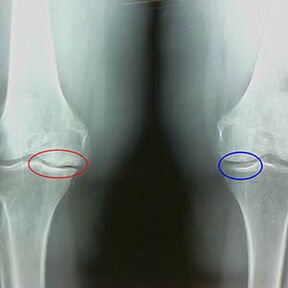

Ankstyvosios x -praėjusio kelio artrozės etapo bruožai:

- smailios briaunų briaunos blauzdikaulyje, kur pritvirtintas kryžiaus formos raištis;

- sąnario tarpo susiaurėjimas medialinėje pusėje;

- Smailūs kaulų condyles kraštai medialinėse pusėse, rečiau šoninėje - priklausomai nuo Valguso vystymosi ar kintamosios sąnario deformacijos.

Antrajam etapui Larsenui Būdingas sąnario tarpo susiaurėjimas daugiau nei 50%, Tačiau tai galima patikrinti tik dinamikoje arba palyginimui su nepanašu į sąnarį.